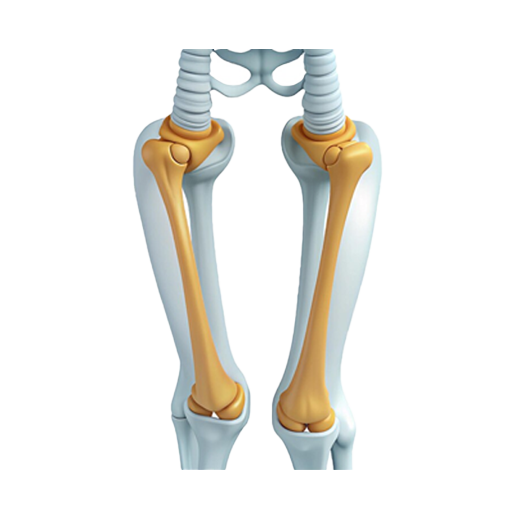

At MM Multi-Speciality Hospital, we are proud to introduce the MISSO Robotic System, the latest innovation in total knee replacement surgery in Namakkal, Tamil Nadu. This state-of-the-art technology redefines precision and personalization in medical procedures, offering patients a safer, more accurate, and efficient surgical experience.

The MISSO Robotic System is equipped with a 6-axis articulated robotic arm, an optical tracking sensor (NDI Polaris), and superior safety sensors to ensure maximum precision during surgery.

The system includes real-time bone movement monitoring and an emergency stop feature. If any bone movement is detected during surgery, the robotic system immediately halts the resection process, enhancing patient safety.

MISSO Robotic System performs fully automatic bone resection without requiring cutting guides, reducing the potential for human error. This automated process enhances surgical accuracy and safety.

The MISSO Robotic System provides surgeons with real-time assistance during surgery, allowing precise adjustments to implant placement and ensuring optimal fit.

Due to the robotic system’s precision, the surgery results in minimal tissue damage, reducing post-operative pain and accelerating recovery.

The system creates patient-specific 3D models from CT scans, allowing surgeons to plan and execute surgeries tailored to each individual’s unique anatomy.

At MM Multi-Speciality Hospital, we are committed to providing the best care using the latest medical technologies. The introduction of the MISSO Robotic System ensures that our patients receive knee replacement surgeries that are safer, more accurate, and less invasive than traditional methods. Our team of expert orthopedic surgeons is trained to leverage the capabilities of the MISSO system to deliver exceptional outcomes.

If you or a loved one is considering knee replacement surgery, MM Multi-Speciality Hospital in Namakkal, Tamil Nadu invites you to explore the benefits of the MISSO Robotic System. Our personalized and precise approach ensures a faster recovery and better post-operative outcomes.